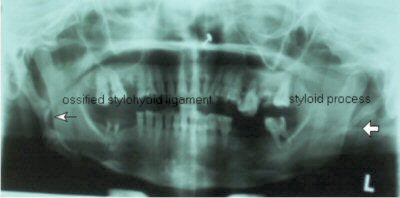

OPG x-ray shows presence of bilateral elongated styloid processes. On the right side, the stylohyoid process is calcified/ossified. Pseudoarticulation of the stylohyoid ligament is seen extending up to the anterior-superior border of the hyoid bone.